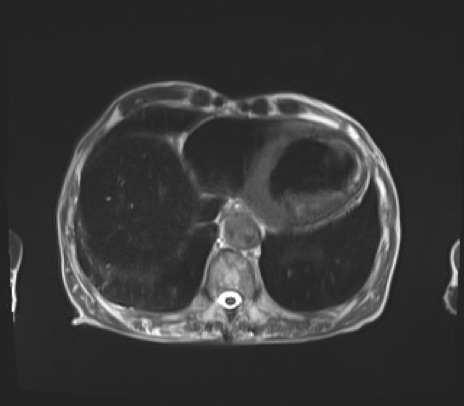

【腹部TIPS】症例38 MRI (T2WI横断像)

【症例】80歳代男性

【主訴】肝内胆管癌の疑いで他院より紹介

肝臓の低吸収域の主な正体は?

MRI